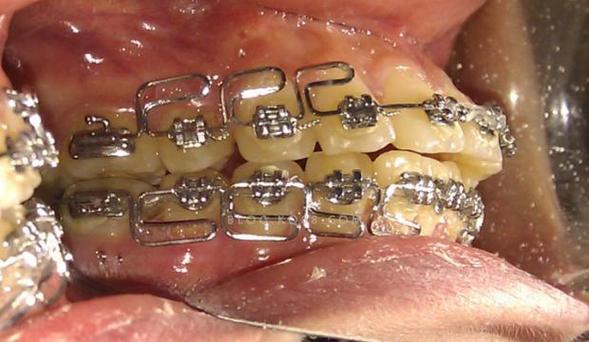

正畸治疗中,弓丝作为引导牙齿移动的核心部件,其位置稳定性直接影响矫正效果,但部分患者可能会遇到弓丝往一边跑的情况,即弓丝在牙弓内偏离正常位置,偏向某一侧牙齿,甚至从托槽中脱出,这种情况不仅可能影响牙齿移动的精准度,还可能引发口腔黏膜不适,需及时关注并处理。